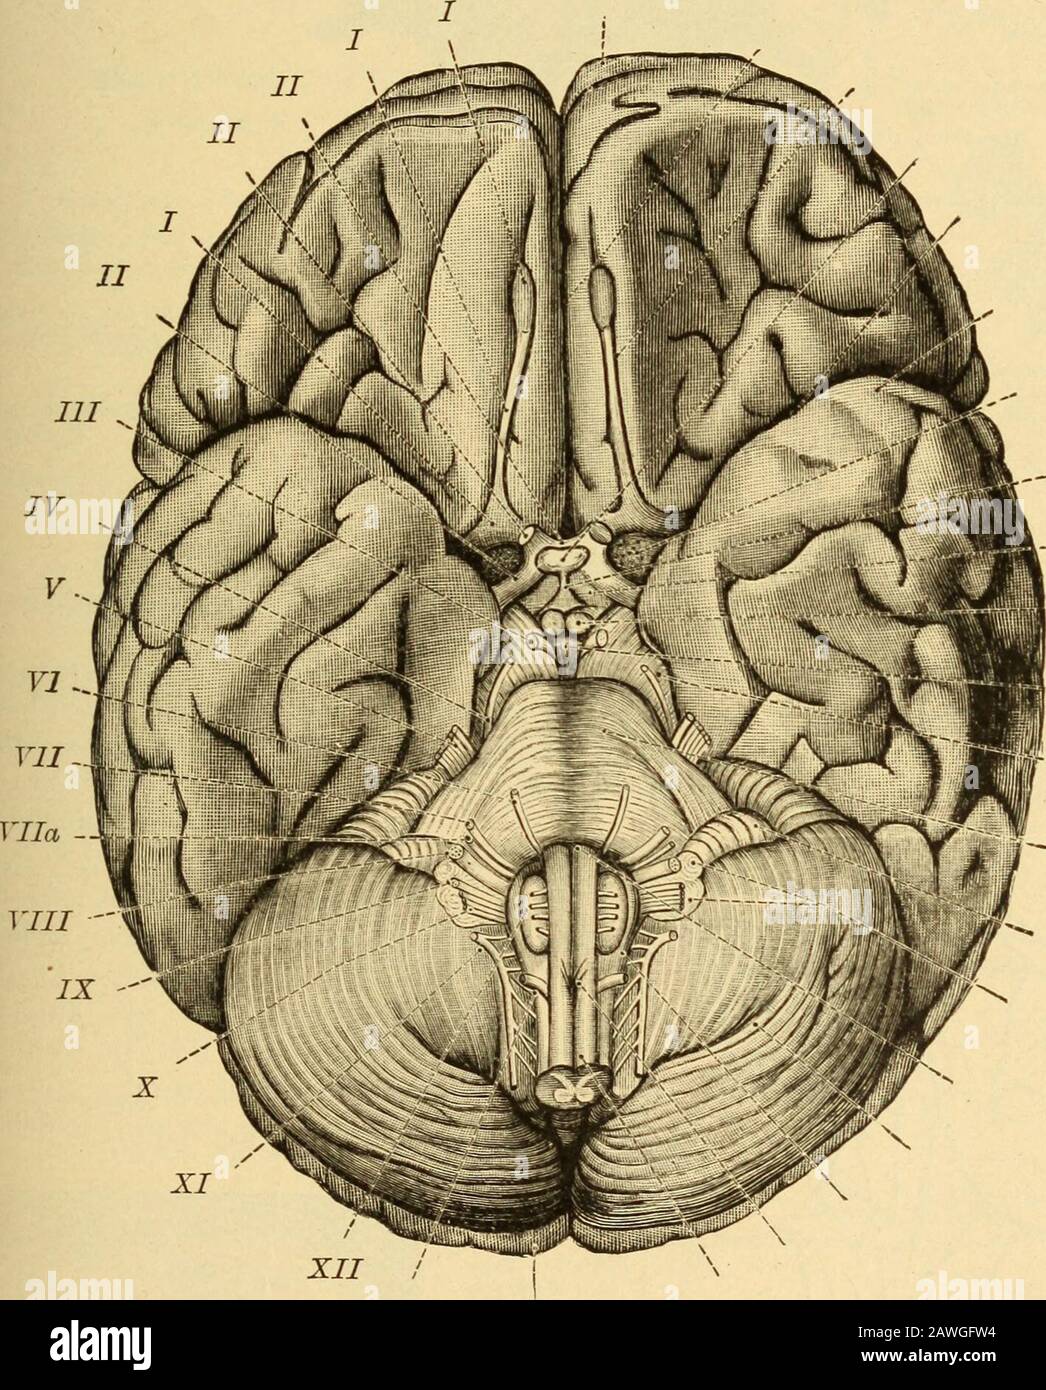

RMRN7XMA–. Anatomie der Katze. Katzen; Säugetiere. 342 NERyOUS SYSTEM. In diesem Teil des Gehirns die Fortsetzung der zentralen Hohlraum ist ein schmaler Kanal, erhält den Namen zerebrale Aquädukt (aqueductus cerebri) oder aquädukt von Sylvius. J. li Abb. 138.-ventrale Oberfläche ov das Gehirn. /-X/I, die zwölf Hirnnerven in Ordnung;/, riechkolben; //, N. opticus; ///, N. Augenmotorischen;/W, N. trochlearis; F, N. trigeminus (I, mandibularnerv; 2, maxillaris Nerv; 3, augenärztliche Nerv; 4, sensorische Wurzel); F/, N. abducens; 17/, N. facialis; 17//, N.; acuslicus LY, N. glossopharyngeus; X, N. vagus; EIN'/, N. acce

RM2AWGFW4–Erkrankungen des Nervensystems .. . "Ortion", die wir als mittleren Regen bezeichnen; hier auch wir. Abb. 43.-Rase der Gehirnnerven von Braix axd. Suchen Sie nach den Hauptabteilungen des Menschen, der Korpora qtiadrigemina (siehe Abb. 44und 45) oben, die Fissure des Sylvius unten und darunter die Faser, die an den oberen Stiegenkeln des Kleinhirns und des Pedunculi-Kleinhirns massiert wird (Abb. 46, 47, 48, 49). Seine Nticlei (Neuronzellen) liegt auf der gesamten Länge des Bodenbelägen des Aquädukts von Sylvius, von seinem frontalen Ursprung fast bis zu seinem kaudalen Ende;5 52 HISTOLOGIE DES ZENTRALEN NERVENSYSTEMS die Kerne des

RM2CE564C–. Erkrankungen des Nervensystems . Abb. 43. – Basis der Braix axd Hirnnerven. Sucht nach ihren Hauptabteilungen im Menschen, der Korpora quadrigemina (siehe Abb. 44und 45) oben die Spalte von Sylvius unten, und darunter die Fasermasse der oberen Pedunkles des Kleinhirns und der Pedunculi cerebri (Abb. 46, 47, 48, 49). Seine Kerne (Neuronenzellen) liegen entlang der gesamten Länge des Aquädukts von Sylvius, von seinem frontalen Ursprung fast bis zu seinem kaudalen Ende;5 52 HISTOLOGIE DES ZENTRALNERVENSYSTEMS die Kerne der trochlearen Nerven liegen posteriorly dort, wo der aque-Ductus liegt